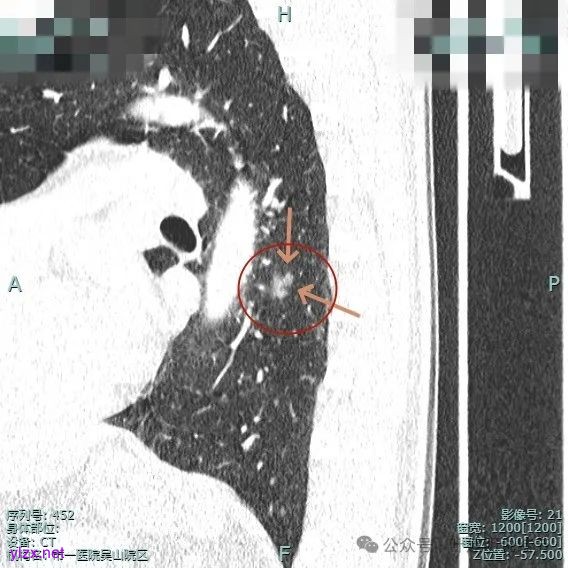

主病灶位于下叶后基底段下肺静脉水平,次病灶在同一层面位靠外基底段交界附近。

薄层上看主病灶不纯,有实性成分,也有血管穿行;次病灶是纯磨,微小的结节,但轮廓与边界较为清楚。

靶重建后见主病灶密度不均,灶内混合密度,整体轮廓较为清楚,表面不平,整体有一定膨胀感。

主病灶混合密度,血管进入;次病灶小且淡,但轮廓清。

2、手术问题:由于主病灶不纯,血管进入与增粗明显,随访是有风险的,应该考虑手术切除。而若主病灶要切除,那么次病灶离它这么近,应该也要考虑一并切除,不然一是只切主病灶后若次病灶刚好位于切缘处,以后观察有无进展困难,二是以后若仍考虑手术,增加难度。从连续层面看以,主病灶位于后基底段靠近背段处,单纯后基底段切除切缘可能不太够;次病灶则靠近外基底段,如果单纯切除后基底段也不安全。经过科室讨论,意见是可以考虑背段加后基底段切除,后基底段与外基底段之间还要往外基底段侧多切过去点。或者后基底段切除,但离断段间平面时向背段侧扩大切除一部分,往外基底段侧也扩大切除一部分。如果切除基底段,还要往背段切过去点,那下叶余下也不多了。手术方式比较纠结。